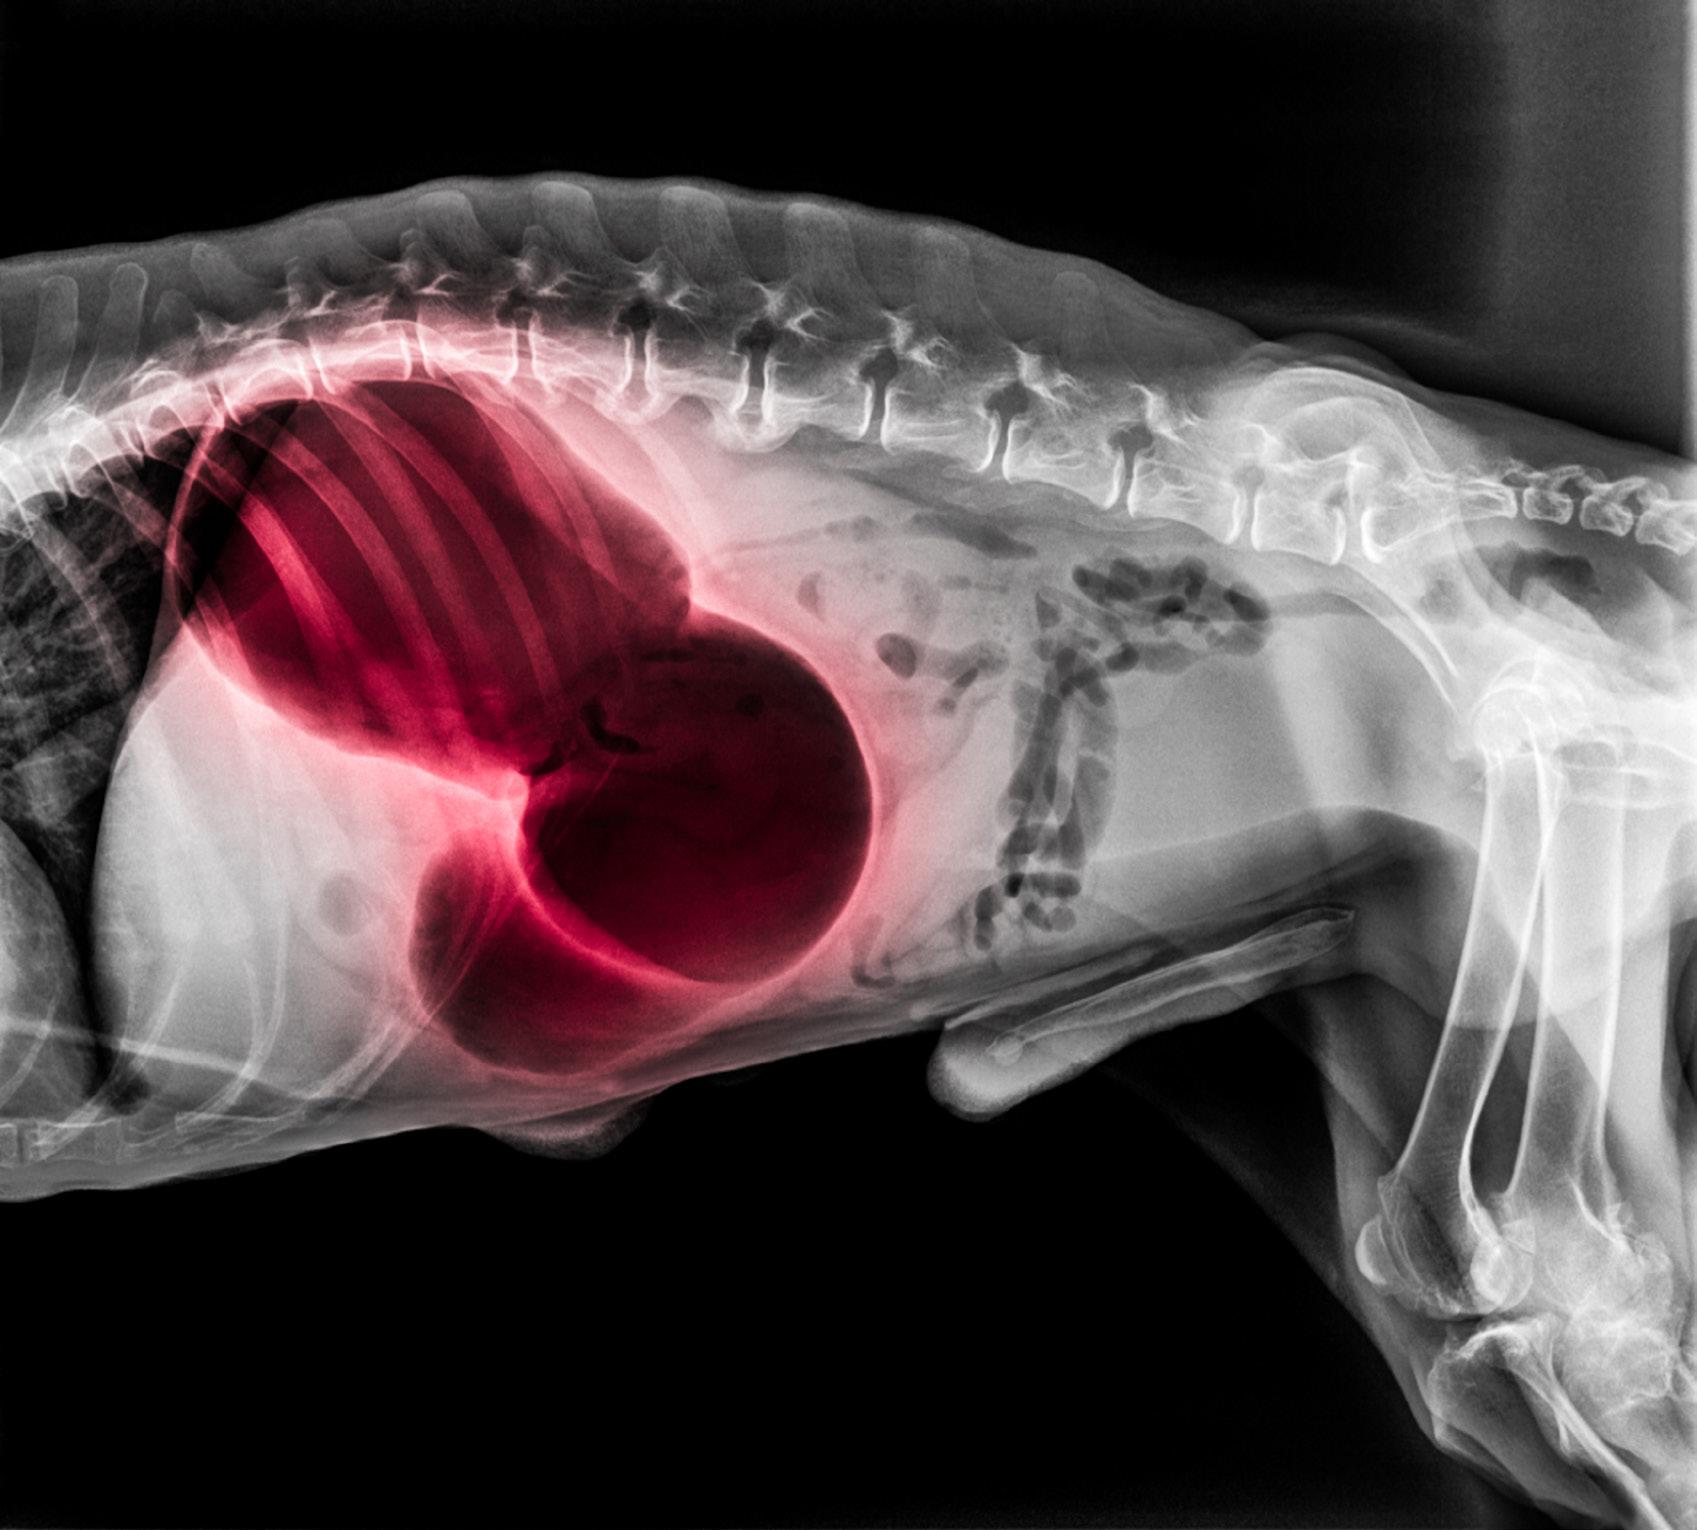

Bloat

A TRUE CANINE EMERGENCY

Deep-chested dogs who look slender from above but have a large distance between their backbone and sternum are the most prone to bloat. This means that the top breeds prone to bloat include:

• Great Danes

• Greyhounds

• Boxers

• Weimaraner

• Standard Poodles

• Doberman Pinschers

WHAT IS BLOAT?

Bloat happens when a dog’s stomach fills with gas or food and stretches to the extent that it causes severe pain. When this happens, the stomach bloats but can also twist. When the stomach twists in this way, it pulls the entrance (the cardia) and exit of the stomach (pylorus) around so that the stomach is completely obstructed. Contents like food, gas and fluid cannot move in either direction. Furthermore, the spleen is attached to the stomach via

DQ | 5C 44 DOG

HEALTH

NOTE

Bloat often occurs in the evening after the dog’s meal. Why this happens is poorly understood.

small blood vessels, which will also twist. This can lead to blood being trapped in the spleen, causing damage.

A twisted stomach is one of the few true canine emergencies that will always require immediate surgical intervention. If surgery is not performed in time, the stomach will rupture.